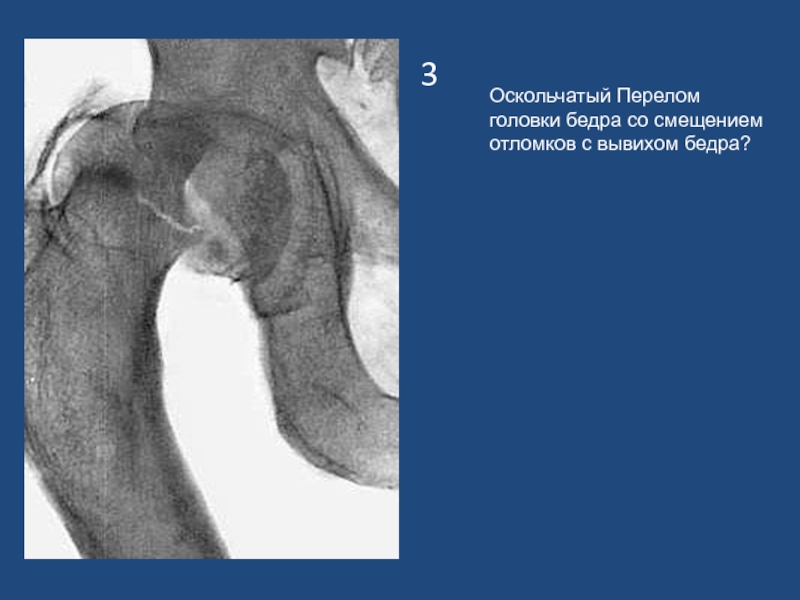

Слайд 43

Оскольчатый Перелом головки бедра со смещением отломков с вывихом бедра?

3Оскольчатый Перелом головки бедра со смещением отломков с вывихом бедра?